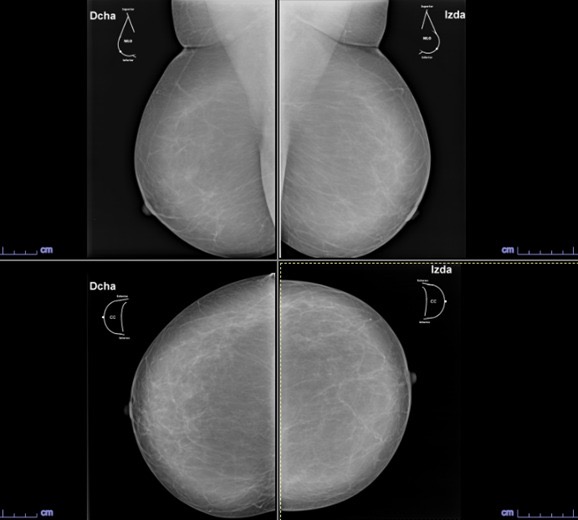

Mamografía Digital

La mamografía es un estudio de diagnóstico por imagen que utiliza bajas dosis de rayos X para obtener imágenes detalladas del tejido mamario. Es una herramienta fundamental para la detección temprana del cáncer de mama y otras patologías mamarias, incluso antes de que sean evidentes al tacto o generen síntomas. Su uso regular en controles preventivos permite salvar vidas al facilitar diagnósticos oportunos y tratamientos más efectivos.

En SCANNER S.A, nuestros equipos digitalizados permiten detectar cambios mínimos en el tejido mamario con alta claridad, permitiendo asi tener un diagnostico preciso y entregar unos resultados reales a nuestros pacientes.